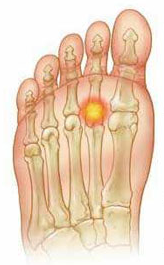

El síndrome de predislocación es un proceso inflamatorio, agudo, subagudo o crónico, que afecta a las articulaciones metatarsofalángicas menores y con frecuencia es no reconocido o mal diagnosticado.

Esta enfermedad es el resultado del fallo de la placa plantar y de los ligamentos colaterales, asociados a patrones anormales de carga del antepié. El progreso de estas alteraciones lleva a la ruptura de la placa plantar que condiciona una inestabilidad crónica de las articulaciones metatarsofalángicas que conduce a una subluxación y luxación de las mismas.

Las roturas de la placa plantar pueden ser la causa más común de dolor debajo de las articulaciones metatarsofalángicas menores, especialmente de la segunda articulación metatarsofalángica.

En la parte inferior de cada articulación de los dedos (excluyendo el dedo gordo del pie), hay una estructura entre la base de la primera falange del dedo y el metatarsiano. Esta estructura se llama placa plantar. Se trata de un espesamiento fibrocartilaginoso plantar de la cápsula articular. Esta estructura mantiene el dedo del pie en la articulación y evita la hiperextensión y que se salga fuera del rango normal de movimiento.

Anatomía de la placa plantar y sus anexos en la articulación metatarsofalángica menor.

La placa plantar está compuesta por fibrocartílago que es una mezcla de fibras de colágeno y cartílago duro. Los tipos de células de la placa incluyen condrocitos y fibroblastos. La orientación de las fibras sugiere que resiste las cargas de tracción en línea con la fascia plantar, así como las cargas de compresión de la cabeza del metatarsiano. Gracias a la presencia de los ligamentos colaterales también puede resistir la flexión hacia los lados. La placa plantar constituye la inserción distal más importante de la fascia plantar. Se observan importantes inserciones de la placa plantar en la falange proximal, en las bandas longitudinales mayores de la fascia plantar y en los ligamentos colaterales. La placa y los ligamentos colaterales forman una envoltura de tejido blando conectado a los lados de la cabeza del metatarsiano. Debido a estos anexos adjuntos y una estrecha asociación con los tendones flexores de los dedos menores del pie, la placa puede ser comparada con el mecanismo sesamoideo de la primera articulación metatarsofalángica.